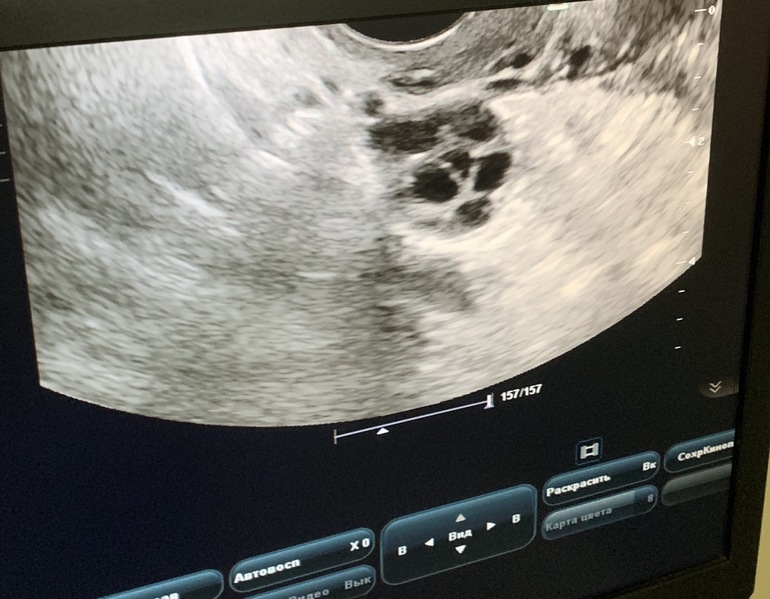

P.S. Фото фолликула после о прилагаю, это что-то странное😂 с мужем очень смеялись, он теперь ждёт мальчика, а я вижу суриката😅🤪

Я ходила на узи на 10 дц, потом случилась о, и на 13 дц я пошла на повторное узи. При первом узи мне узист показала это фолик с прошлого цикла, но отметила что он немного кривой, с прошлого цикла и что он не лопнет.

В прошлом цикле он как раз не лопнул, отслеживала по узи, о не было, он вырос до 24 мм точно. Следующее узи только на 10дц вот делала.

При крайнем узи так же узист отметила жидкость и сказала что этот фолликул сдулся как будто он лопнул.

Думаю на него, так как на 10 дц дф был 9,5 мм. Или это он мог лопнуть?

Да, но она сказала что он лопнул но так как был большой ещё остался и его видно.

😂😂😂спасибо за позитив) согласна с вами во многом, но по всем признакам фолликул который на фото - с прошлого месяца, это 100%. А лопнул он или какой-то фолик рядом это уже точно она мне не скажет. Говорит: лопнул старый, при этом остался в яичнике, из него вытекла жидкость 😂😅